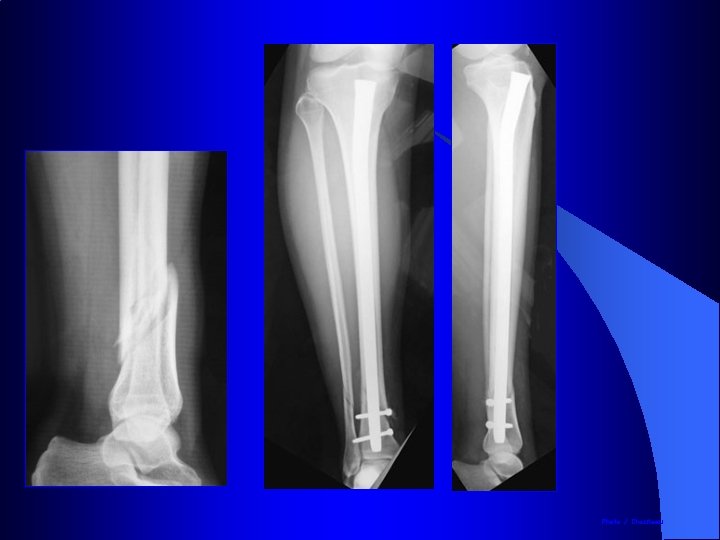

Qualité du cal osseux après enclouage du tibia à foyer fermé Avantages de l’enclouage Préservation de l’hématome Pas de dépériostage Cal volumineux

Clou de tibia Verrouillage proximal Verrouillage distal Photo J. Chouteau